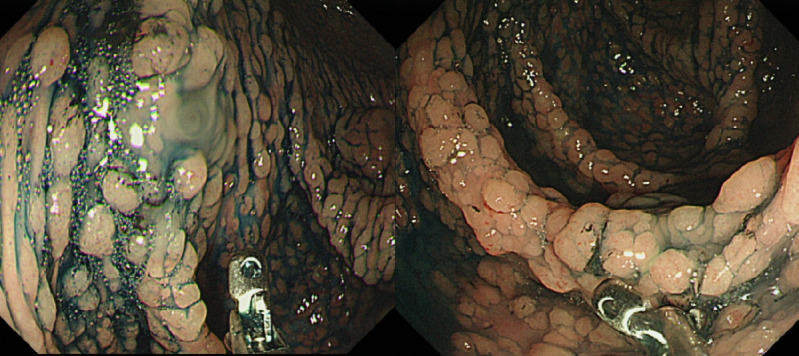

遗传性结直肠癌是一种由基因突变引起的癌症。有结直肠癌家族史或已知有遗传综合征的人患这种疾病的风险会增加。筛查和监测是控制遗传性结直肠癌风险的重要手段。筛查包括一系列可检测结肠和直肠癌前病变或癌症病变的检查。监测包括定期随访检查,以监测疾病的进展并发现新的发展。筛查和监控检查的频率和类型可能因个人的风险因素、遗传特征和病史而异。不过,遗传性结直肠癌的早期发现和治疗可显著改善患者的预后并降低死亡率。通过实施全面的筛查和监测策略,医疗服务提供者可以帮助有遗传性结直肠癌风险的人及时接受干预,并就其健康做出明智的决定。遗传性结直肠癌筛查和监控检测的具体例子包括结肠镜检查、基因检测和成像检测。在这篇综述文章中,我们将详细讨论遗传性结直肠癌的筛查和监测。

Hereditary colorectal cancer is a type of cancer that is caused by a genetic mutation. Individuals with a family history of colorectal cancer, or who have a known hereditary syndrome, are at an increased risk of developing the disease. Screening and surveillance are important tools for managing the risk of hereditary colorectal cancer. Screening involves a combination of tests that can detect precancerous or cancerous changes in the colon and rectum. Surveillance involves regular follow-up examinations to monitor disease progression and to identify new developments. The frequency and type of screening and surveillance tests may vary depending on an individual's risk factors, genetic profile, and medical history. However, early detection and treatment of hereditary colorectal cancer can significantly improve patient outcomes and reduce mortality rates. By implementing comprehensive screening and surveillance strategies, healthcare providers can help individuals at risk of hereditary colorectal cancer to receive timely interventions and make informed decisions about their health. Specific examples of screening and surveillance tests for hereditary colorectal cancer include colonoscopy, genetic testing, and imaging tests. In this review article, we will discuss detailed screening and surveillance of hereditary colorectal cancer.